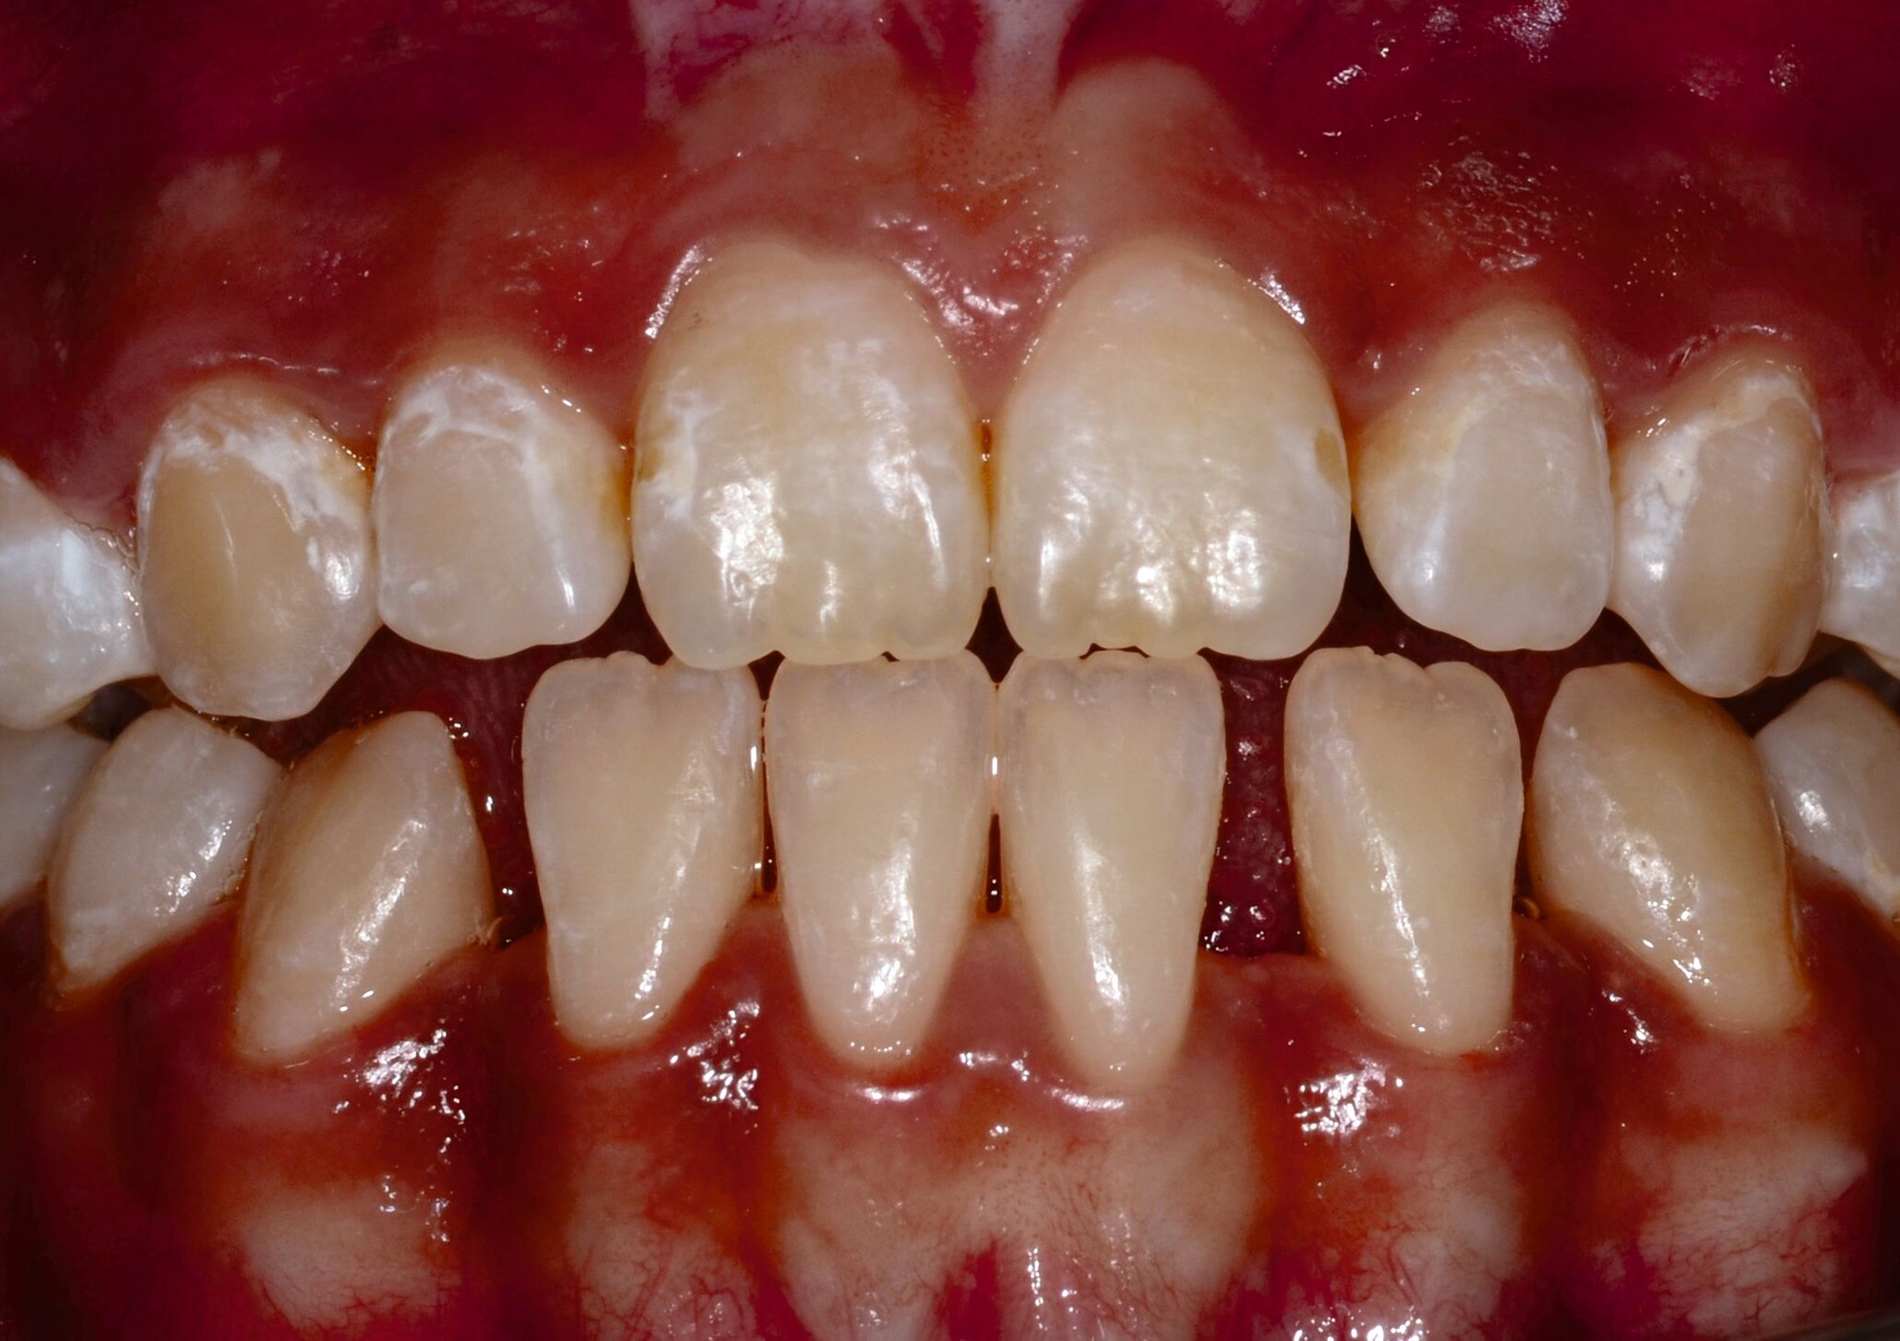

... für Zahnformkorrekturen im Frontzahnbereich

Ähnliche Ergebnisse wurden bei Zahnformkorrekturen erzielt. Die untersuchten Studien berichteten über hohe bis sehr hohe Überlebensraten von Komposit-Restaurationen mit Nachbeobachtungen bis zu 15 Jahren. Beim Vergleich mit indirekten Keramikveneers zeigten diese zwar höhere Überlebensraten, doch basiert diese Schlussfolgerung auf einer einzelnen Studie mit kurzer Nachbeobachtungszeit [Meijering et al., 1998]. Die Nutzen-Schaden-Bewertung spricht klar für den Einsatz von Kompositen zur Zahnformkorrektur im Frontzahnbereich (Abbildung 3), aufgrund der hohen Überlebensraten, der guten bis ausgezeichneten klinischen Qualität, der Reparierbarkeit und der geringeren Invasivität im Vergleich zu Keramikveneers. Der elektive Charakter dieser Verfahren sollte bei der Gesamtbeurteilung berücksichtigt werden. Für diese Behandlungen wird ein minimalinvasiver oder nichtinvasiver und präventionsorientierter Ansatz empfohlen.